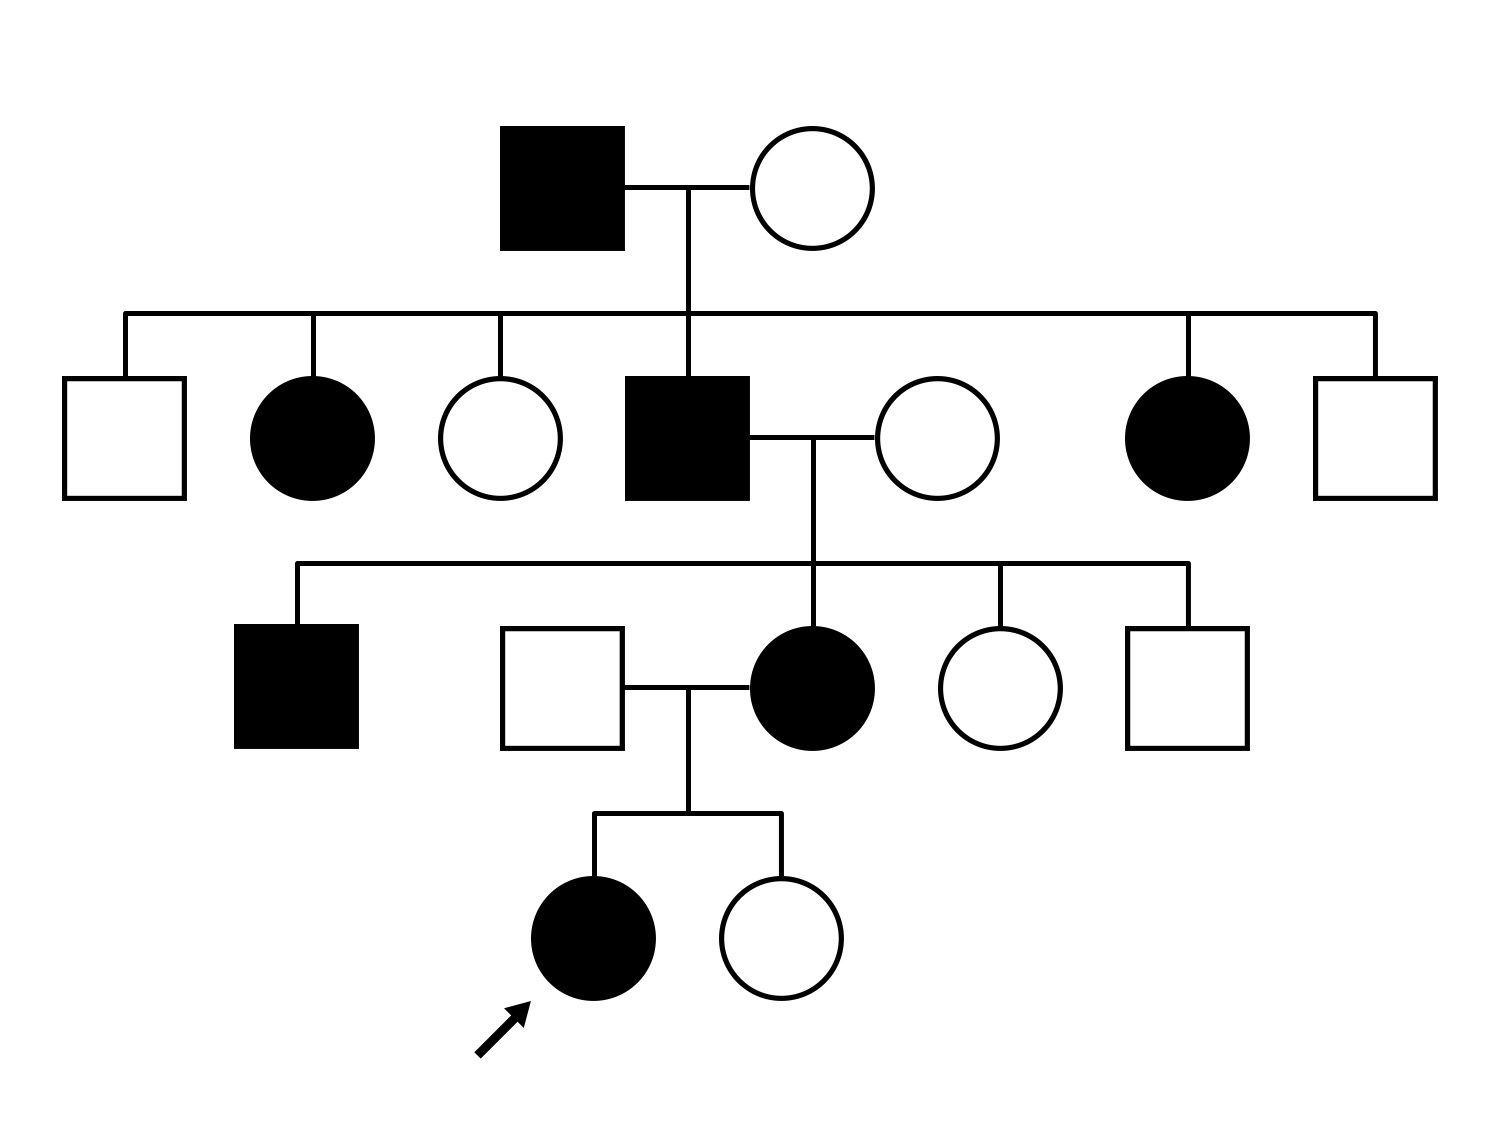

AD CSNB (IA2fii)

AD CSNB (IA2fii)

History

This 44 year old woman has had very poor vision in dim light for her entire life. She vividly remembers running into a picnic table on a bicycle in a campground as a child.